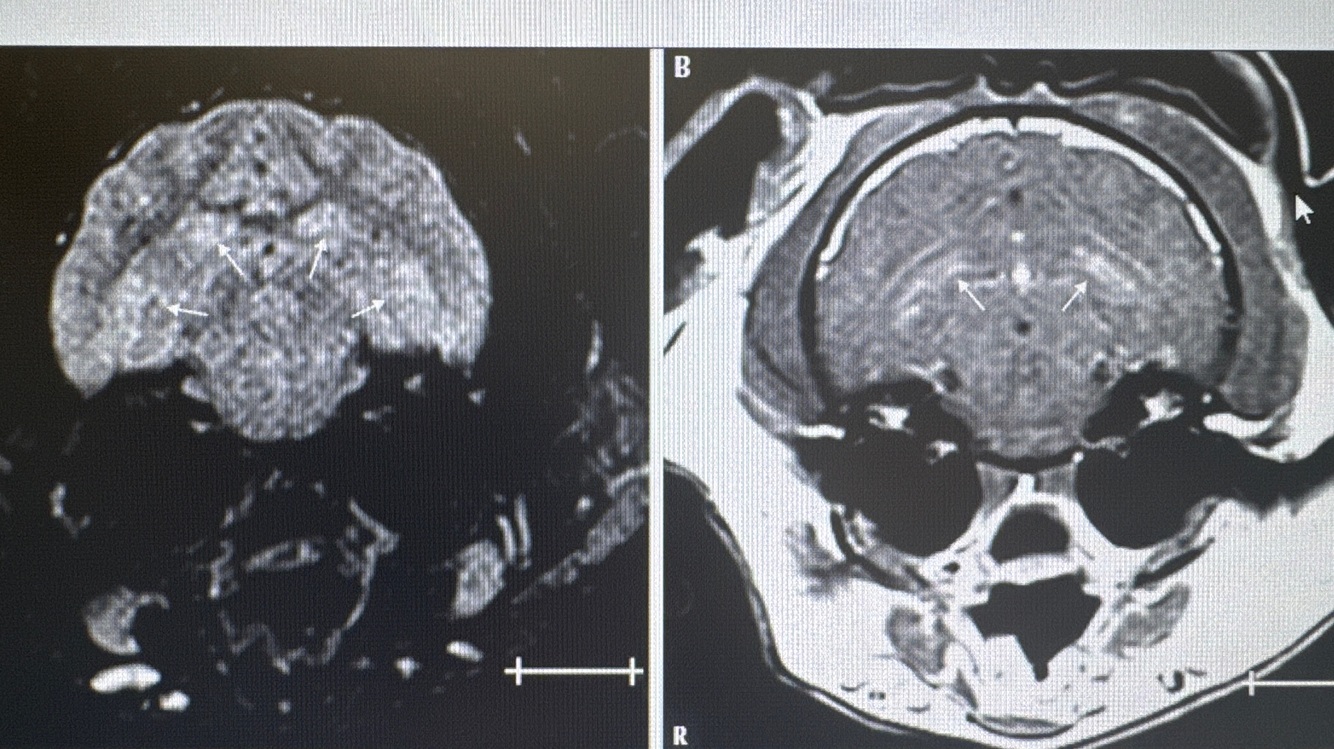

Name MRI sequences, planes, level and describe changes

• left FLAIR, right T1 post contrast

• transverse

• level of the hippocampus

• bilateral symmetrical hyperintensity in the dorsal and ventral hippocampus in FLAIR

• marked heterogenous contrast enhancement in T1